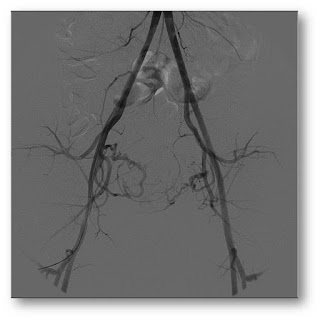

Esta imagem mostra

uma arteriografia de todos os vasos da pelve. Nela, o médico consegue

identificar as artérias que levam sangue e nutrem os miomas